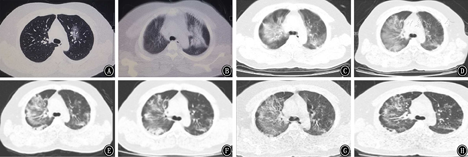

2020年1月24日当地县医院胸部CT示左肺磨玻璃影;右肺中叶条索。1月29日当地县医院CT肺部病变较前明显增多。2月1日衡水市第三人民医院胸部CT示双肺符合COVID-19影像表现[11]。2月9日与2月1日比较,右肺上叶片状阴影范围增大,余双肺病变略显减少。2月13日与2月9日比较,双肺病变范围缩小,双肺病变实性成份增多。2月17日与2月13日比较,双肺病变范围稍缩小,双肺病变实性成份较前稍减少。2月21日与2月17日比较,双肺病变范围稍缩小,双肺病变吸收好转。2月23日与2月21日比较,双肺渗出病变较前吸收、减少,病变范围较前缩小,纤维化较前明显。具体情况见图1。